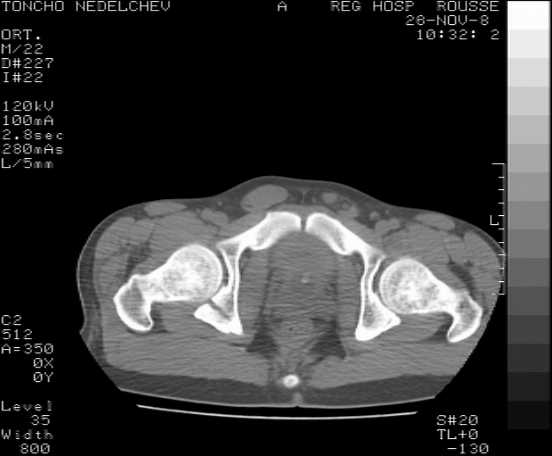

[Ortho] Acetabular fracture

Here are some more axial images. What is your opinion as for the timing of the operative treatment?